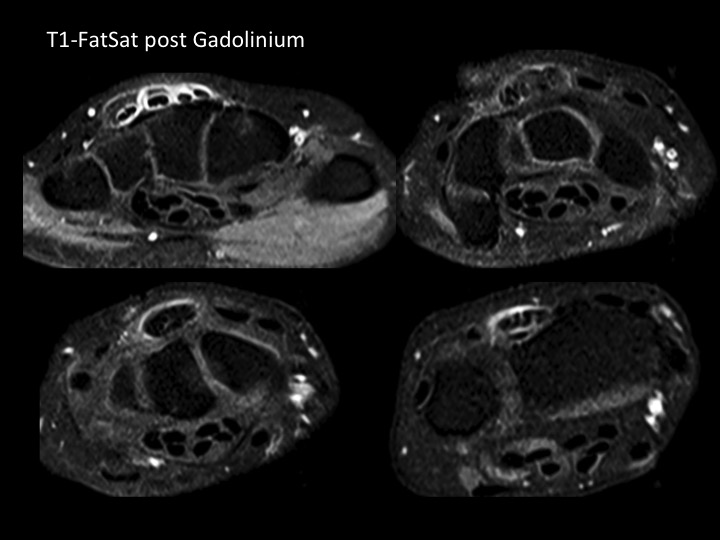

54F 2 months dorsal pain and swelling, suspect ganglion

The mass is centered over the CMC joints, and corresponds to stenosing tenosynovitis of the 4th extensor compartment. There is no ganglion (more commonly in proximity to the SLL). At the level of carpus, there is tendinosis and probable partial tearing of multiple common extensor tendons. At the level of the radiocarpal joint, all of the EDC tendons clump together, with enhancement of the thickened extensor retinaculum. There is pre-and post- stenotic dilation with effusion and enhancing synovium in the wrist and hand. This was referred by a hand surgeon. I have seen many cases like this on MRI and US and am always amazed that there is no suspicion of stenosing tenosynovitis and that ganglion is favored. I would imagine there would be painful limitation to finger extension. In this patient, there is no joint narrowing or articular synovitis. I have noticed this more commonly in women and am intrigued that the attached article implies that there may be some association to estrogen stimulation and deficits. Reference article.

4th extensor compartment tendinosis and stenosing tenosynovitis